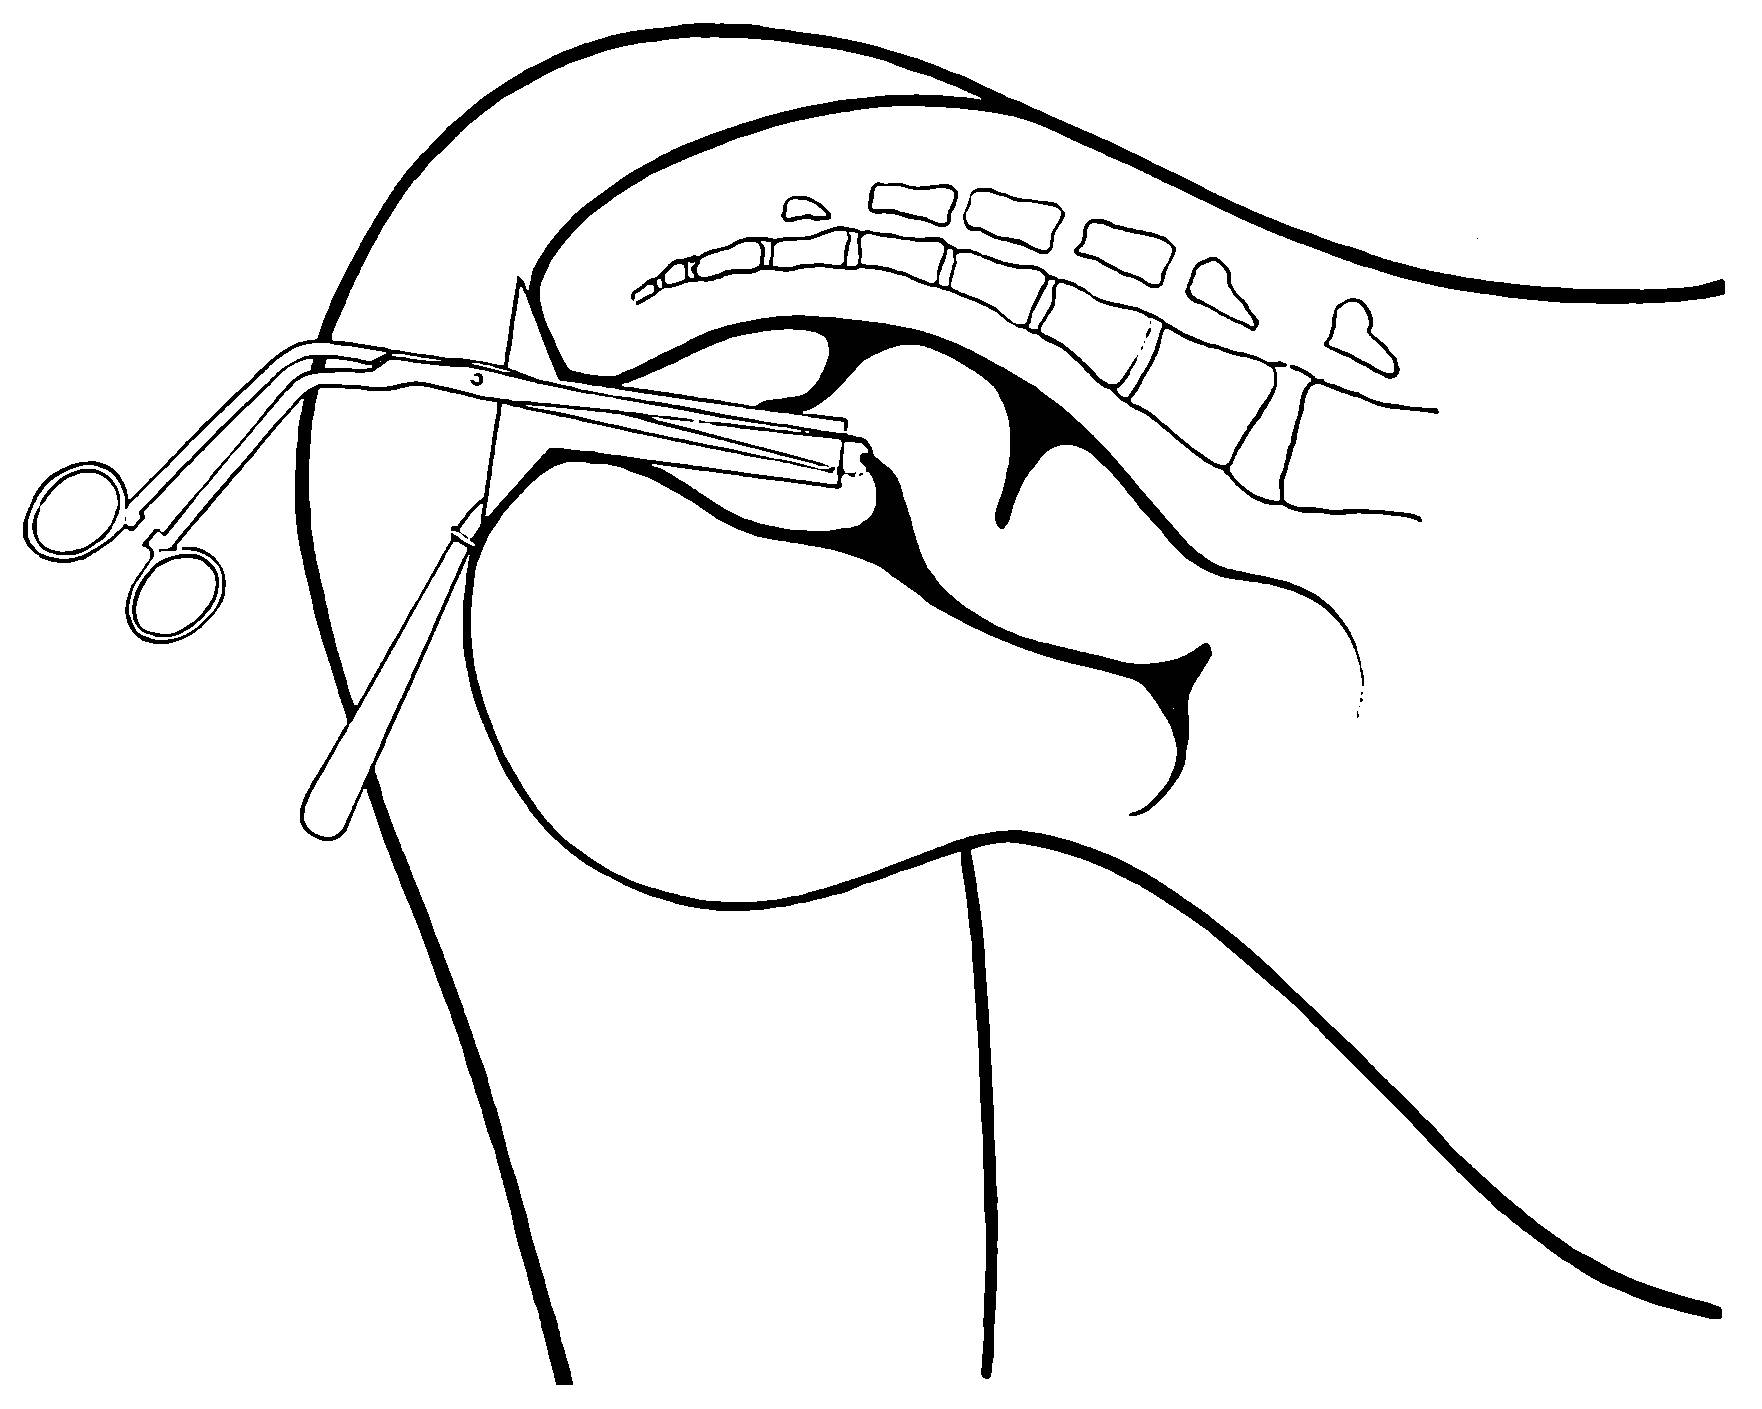

Fig. 1.—Positions of the hands for the practice of the simplest method of proctoscopy.

Fig. 2.—Positions of the fingers for the practice of the simplest method of proctoscopy.

3. The physician is to close his hands and to point each index-finger as shown in the accompanying illustration (Fig. 1). The wrists are to be crossed, the hands placed back against back, and the nails of the index-fingers placed one against the other, as shown in the accompanying illustration (Fig. 2). The physician is to lubricate these fingers and gently insinuate them through the anus and place their ends beyond the borders of the levatores ani. This accomplished, the anus is to be divulsed in the direction of the ischial tuberosities, by the physician forcibly parting his fingers as is shown in the accompanying illustration. Under this manipulation the rectum becomes atmospherically inflated.

Now, provided the physician lowers his head to the level of his fingers and then rises again, or stoops, or moves a little from side to side, he may command under his eye a view of the interior of the atmospherically inflated rectum to the depth of six or eight inches (15.24 or 20.32 cm.), and in some instances he may behold even a part of the sigmoid flexure.